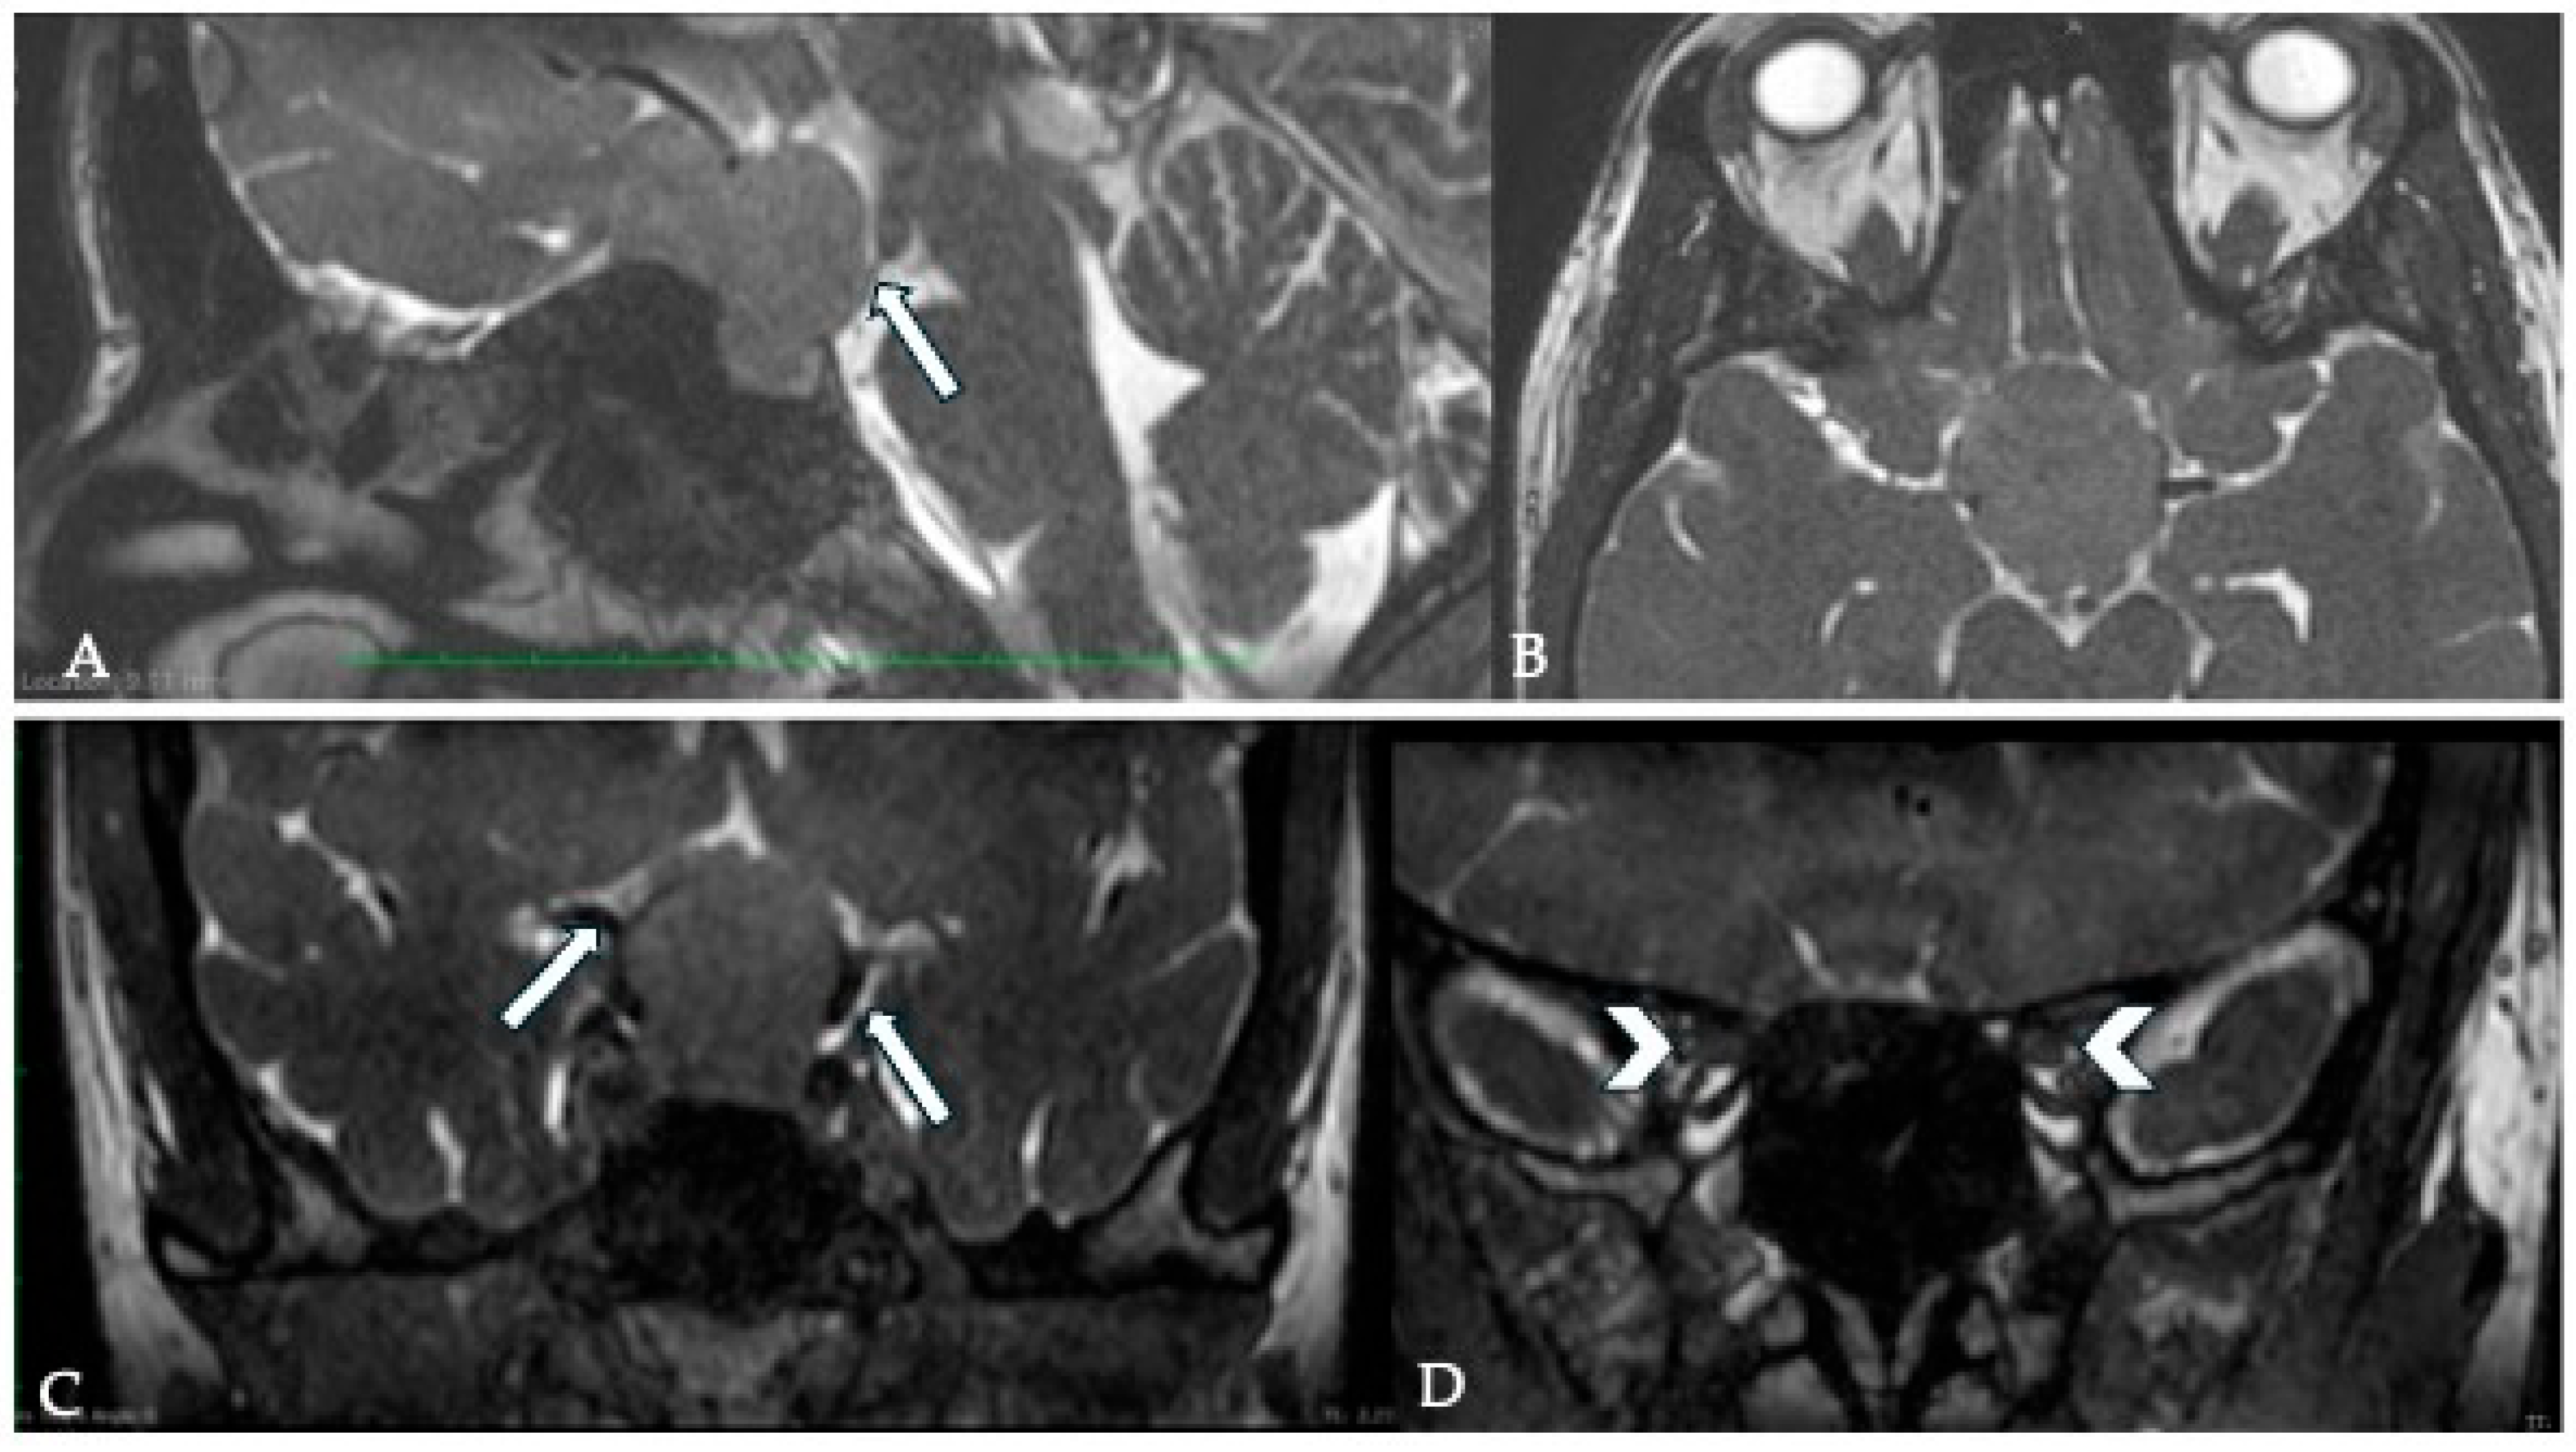

8. Cavernous Sinus Involvement (CSI)

8.1. Surgical Significance

8.2. Imaging Evaluation

8.3. Key Surgical Considerations